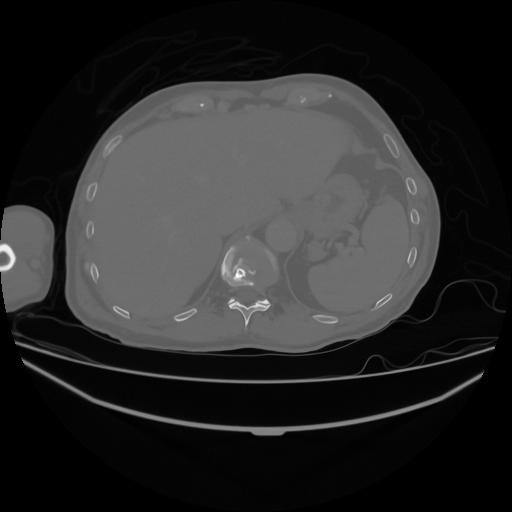

5 CUERPO,CE,Vol,1.0,CUERPO,,